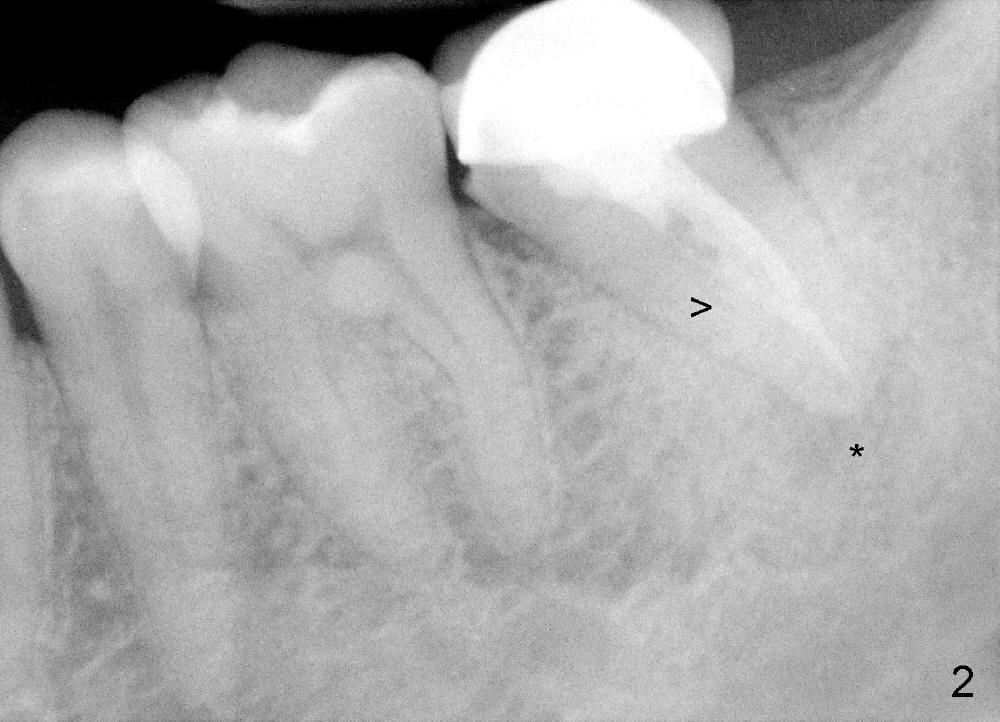

冷先生四五年前来诊所诊治,左下第二磨牙(图一:18)做过根管治疗,牙冠,偶尔不适,近中牙冠不密和(*,open margin),估计迟早会脱落,到时再重做根管治疗(retreat)好像为此不晚,病人听了这个方案没意见。三年半过去了,一切如旧,左下第二磨牙根尖阴影仍存在(图二*),仿佛一个根管没充填(箭头),病人同意拔除左上智齿(图一,四:16)。又过半年左下牙冠终于脱落,病人自动要求重做根管治疗,没充填根管找到,充填(图三箭头),之后症状消失,他很高兴。